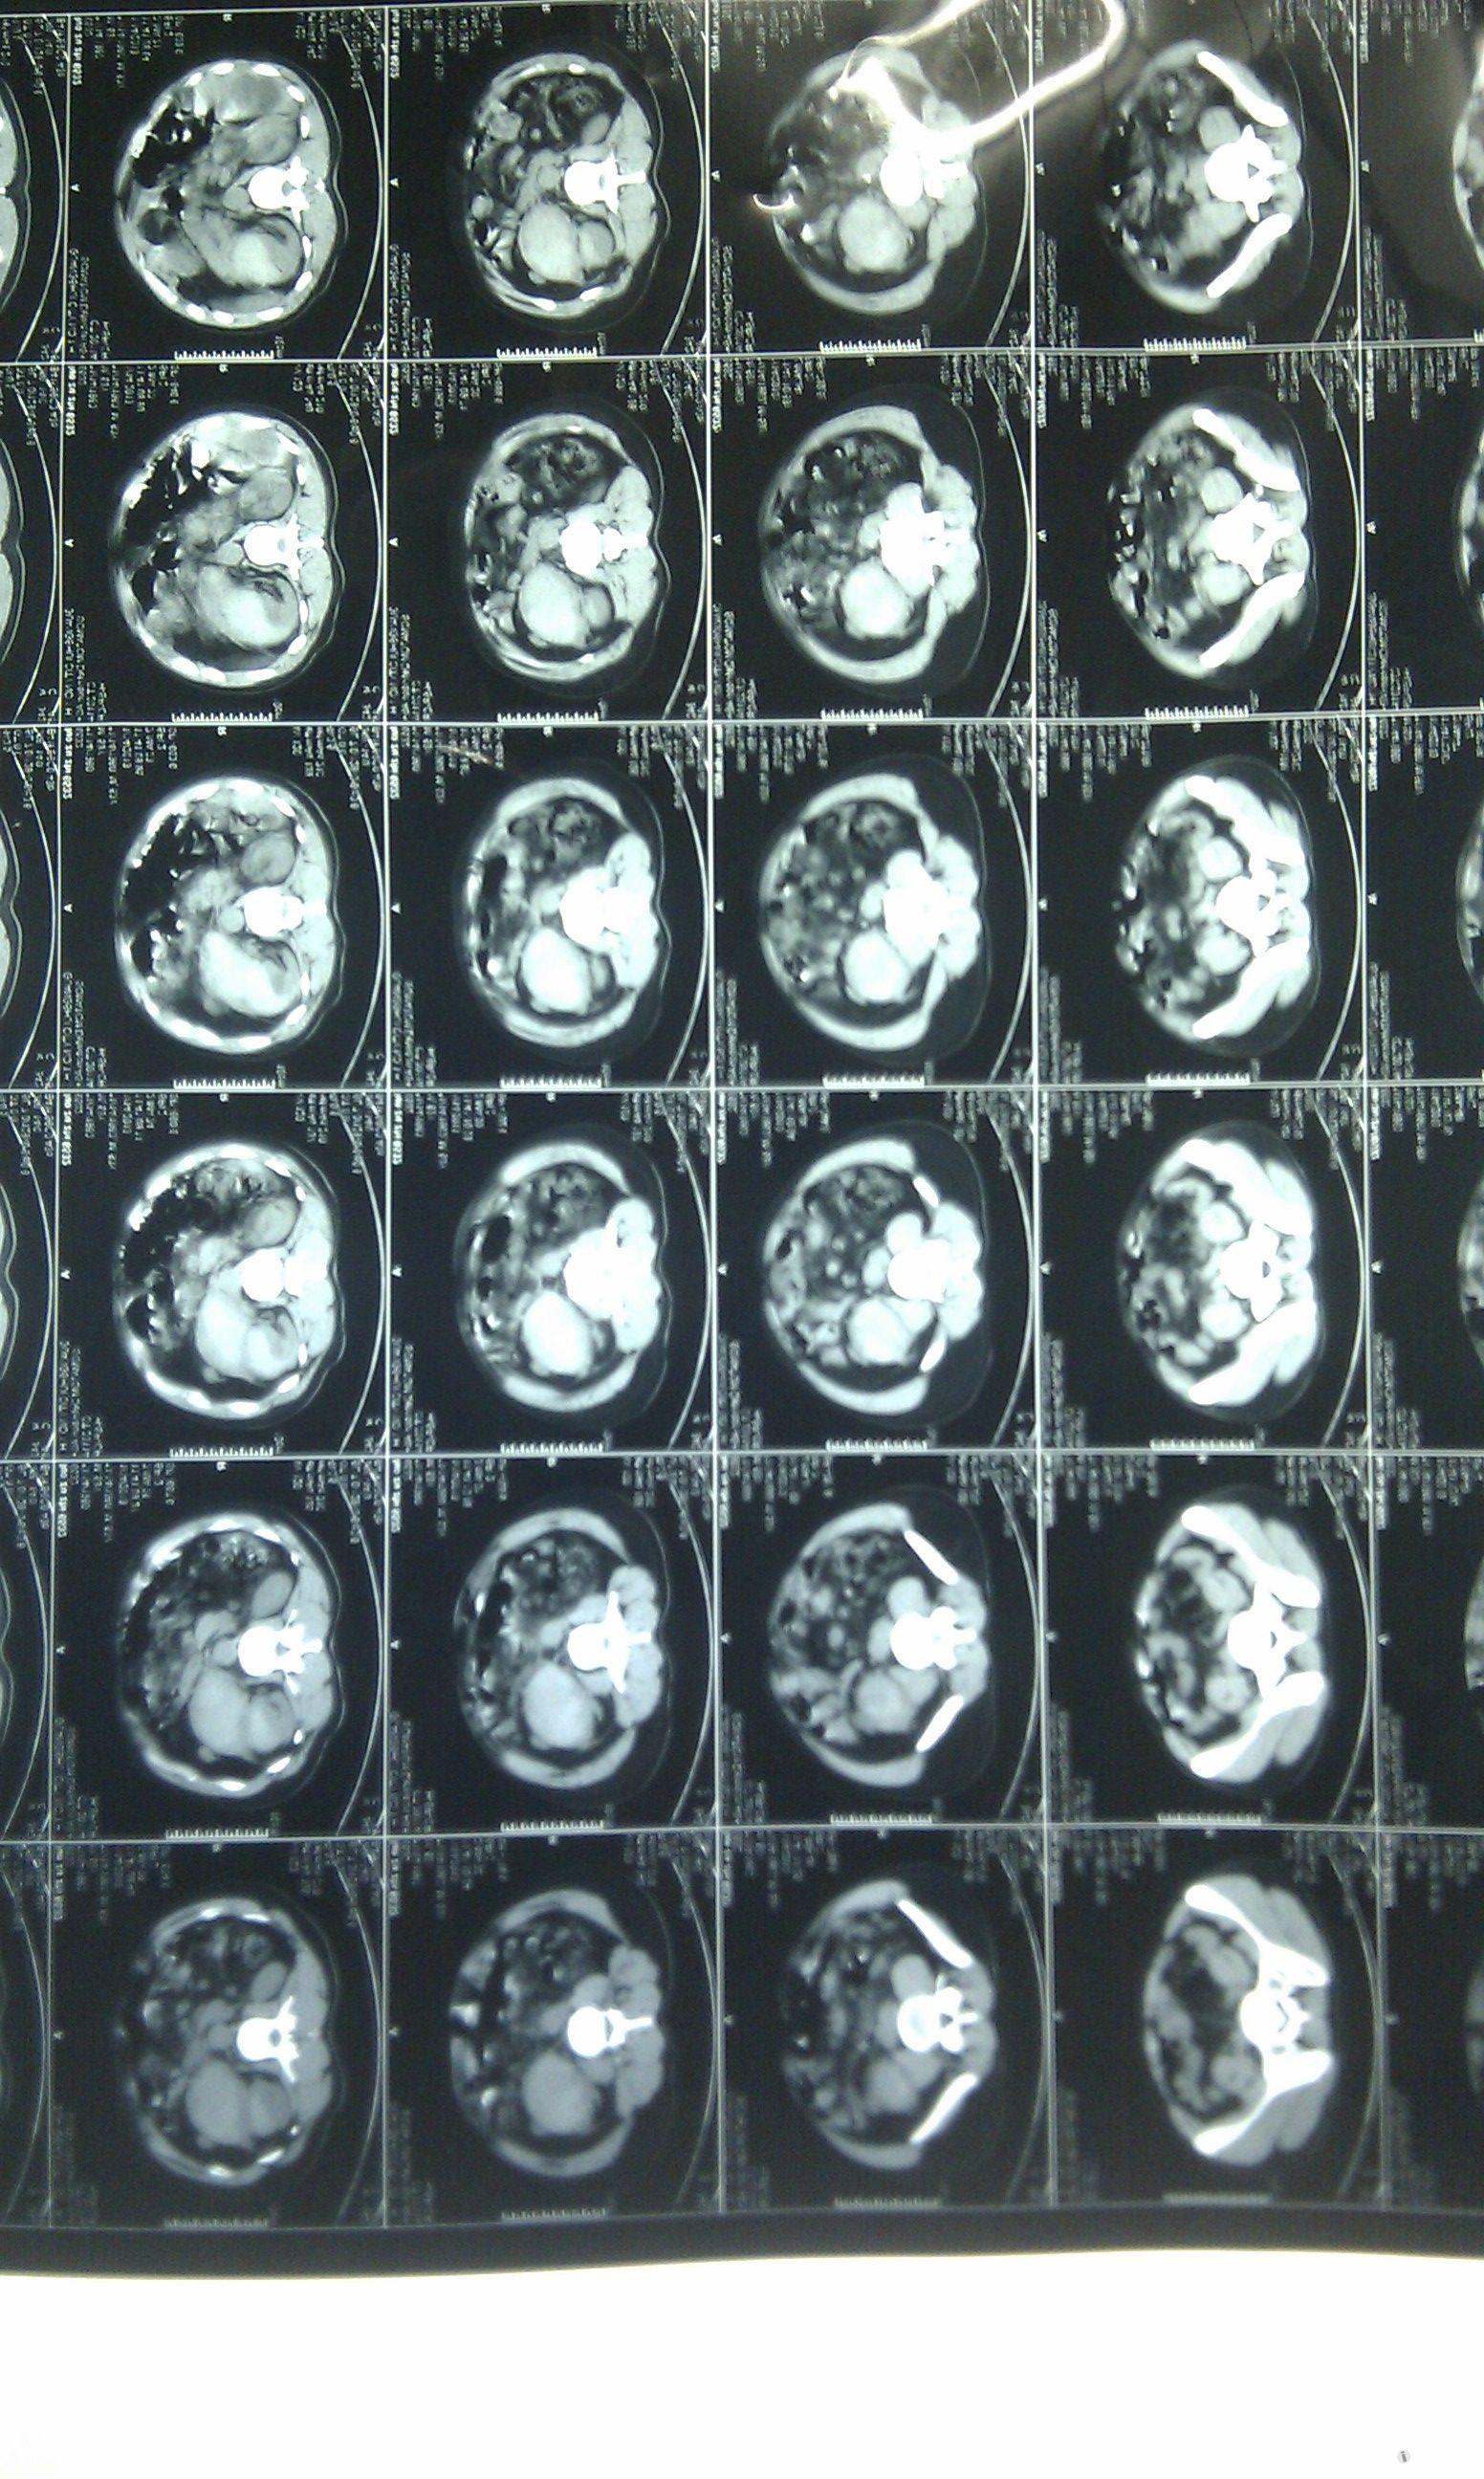

无血尿,入院查ct提示:黄箭头所指为右肾包膜下高密度影,考虑血肿;绿